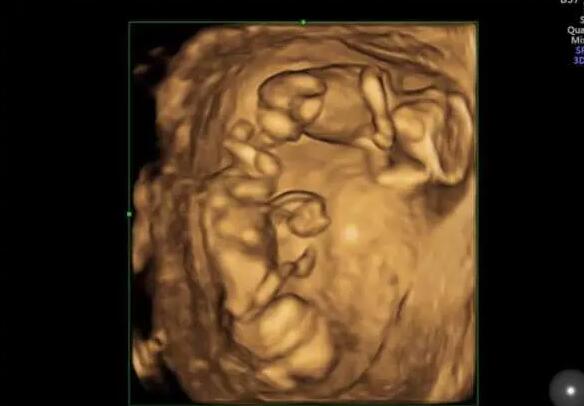

嬰兒床上,雙胞胎寶貝粉嫩的小手緊緊攥著媽媽的手指,那么溫暖那么有愛。誰會想到,不久前兄弟倆剛經歷一場生死之戰,90余天在醫護人員的精心治療和呵護下,勇敢的寶貝們創造生命奇跡,回到爸爸媽媽的懷抱。15日,這對超早產雙胞胎寶寶終于康復出院,他們也是西安交大一附院成功救治的西北最小胎齡超早產雙胞胎試管嬰